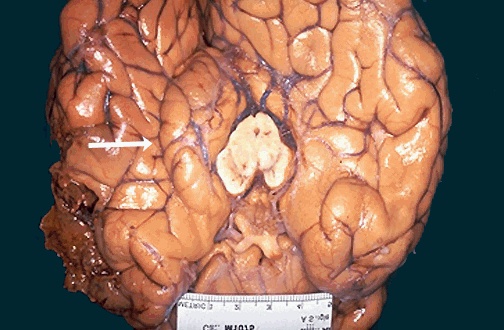

| Acute brain swelling in the closed cranial cavity is serious. Swelling of the left cerebral hemisphere has produced a shift with herniation of the uncus of the hippocampus (medial temporal lobe) through the tentorium, leading to the groove seen at the white arrow. [Image contributed by Jeannette J. Townsend, MD, University of Utah] |